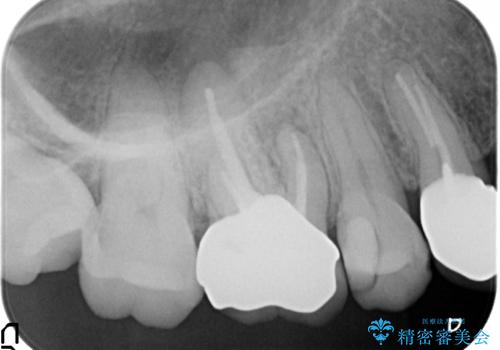

- 右上の奥歯でものを咬むと痛むため他院を受診したが、治療は難しいと言われたため当院にいらっしゃった方の症例です。

再根管治療を行い症状の緩解を確認後、オールセラミッククラウンによる補綴を行いました。